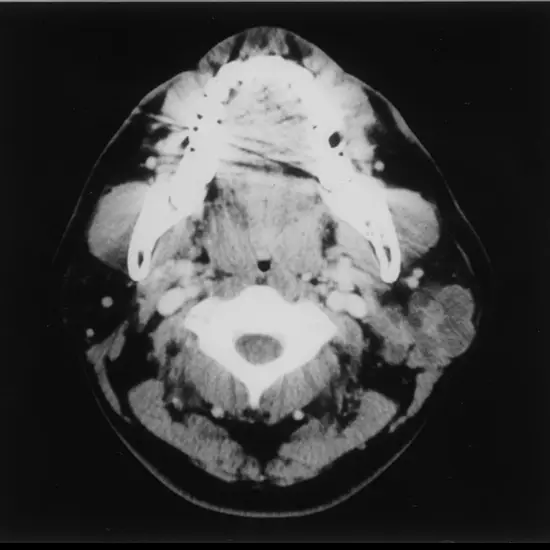

Non-contrast computed tomography of the parotid gland is a diagnostic imaging  technique that is used to diagnose malignancy, if there are any changes to the lymph nodes in the neck and detect whether the cancer has spread.

NCCT parotid is a non-contrast computed tomography to create a cross-sectional image of the parotid gland and its internal structure and pathology.

NCCT parotid is a diagnostic imaging technology that is used to produce scan images in a cross-sectional form, the scan images are produced for the parotid gland along with the pathology associated and its internal structure.

The NCCT parotid scan stands for a non-contrast computed tomography scan that is conducted to visualise and diagnose conditions associated with the parotid gland.